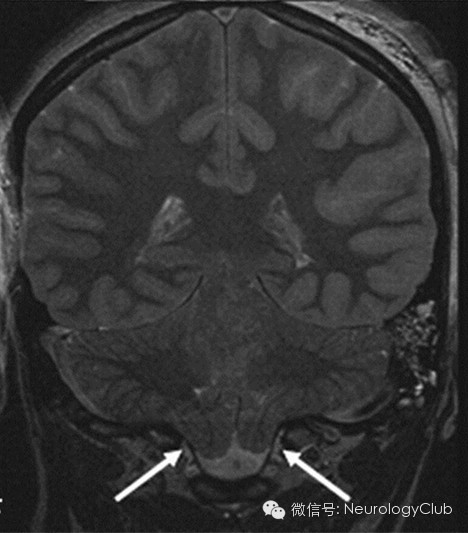

增强扫描时硬脑膜弥漫性增强增厚是颅内低压综合征的最具特征性表现,也是阳性率最高、出现最早的MRI表现。呈不间断的线样增强,无局限性结节,同时经常伴有硬脑膜增厚和皮层静脉的扩张,但从不累及软脑膜。

(3)静脉结构充盈(Engorgement of venous structures)